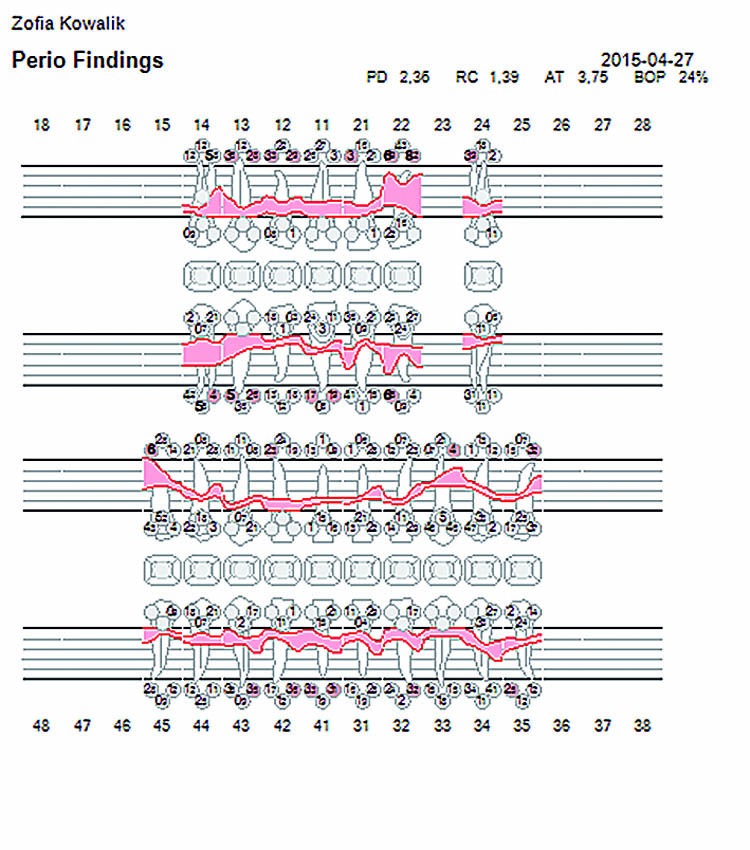

Η λεπτομερής κλινική εξέταση θα περιελάμβανε, μεταξύ των άλλων, στοιχεία σχετικά με το βάθος των περιοδοντικών θυλάκων (ΒΘ), την αιμορραγία κατά την ανίχνευση (ΑΚΑ) και τον δείκτη πλάκας (ΔΠ).

Πριν τη θεραπεία, η ασθενής υποβλήθηκε σε διαδικασία υποουλικού καθαρισμού με ξέστρα υπερήχων. Μετά τον καθαρισμό, η κλινική κατάσταση της ασθενούς βελτιώθηκε. Στη συνέχεια, εφαρμόστηκε ένα laser Nd:YAG για την αποστείρωση και την απολύμανση των περιοδοντικών θυλάκων (Εικ. 3 έως 7) και laser Er:YAG για την απομάκρυνση της υποουλικής τρυγίας (Εικ. 8 έως 12).

Για την τελική απολύμανση και αποστείρωση του πήγματος ινικής, εφαρμόστηκε και πάλι το laser Nd:YAG (Εικ. 13 και 14). Στην Εικ. 15 φαίνεται η κατάσταση αμέσως μετά τη χειρουργική με laser Er:YAG και την απολύμανση των περιοδοντικών θυλάκων με Nd:YAG